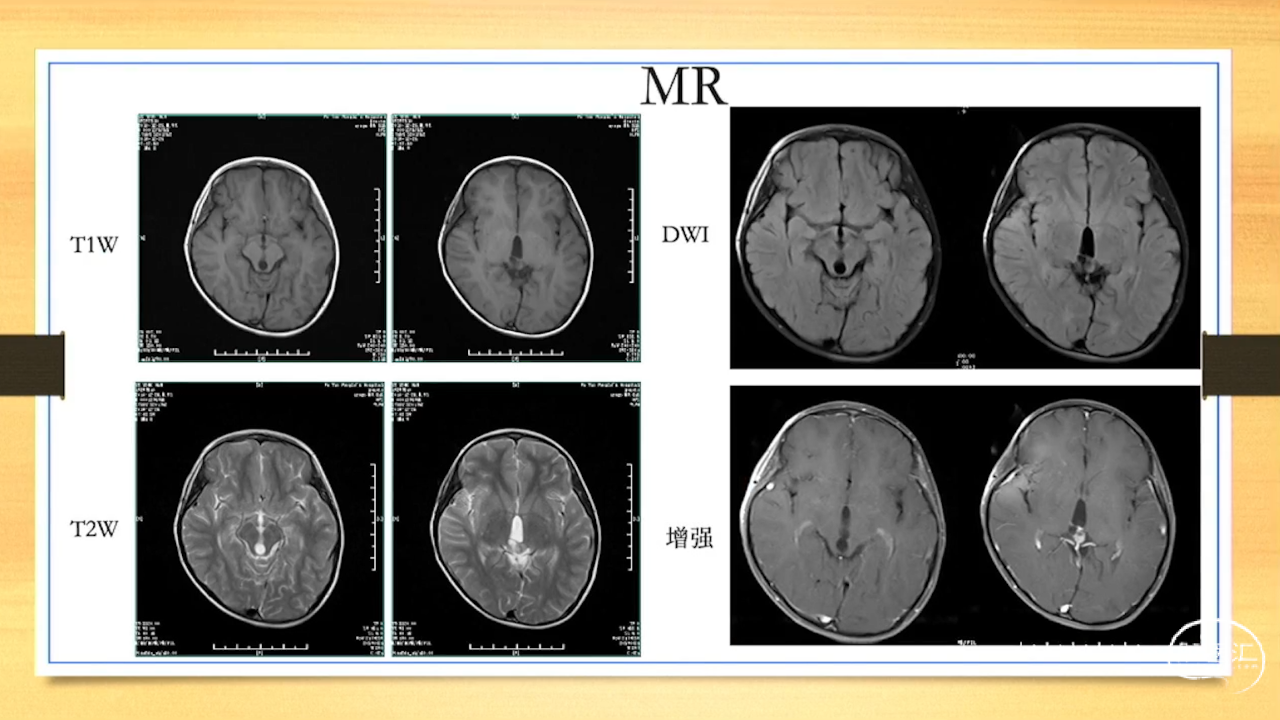

张荣教授:儿童颅内生殖细胞瘤的手术治疗

颅内生殖细胞肿瘤的治疗是手术、放疗、化疗、内分泌及其他多学科的整合治疗。及时、精准、合理的手术治疗是iGCT患者提高生存率、降低并发症、改善神经内分泌功能的关键。